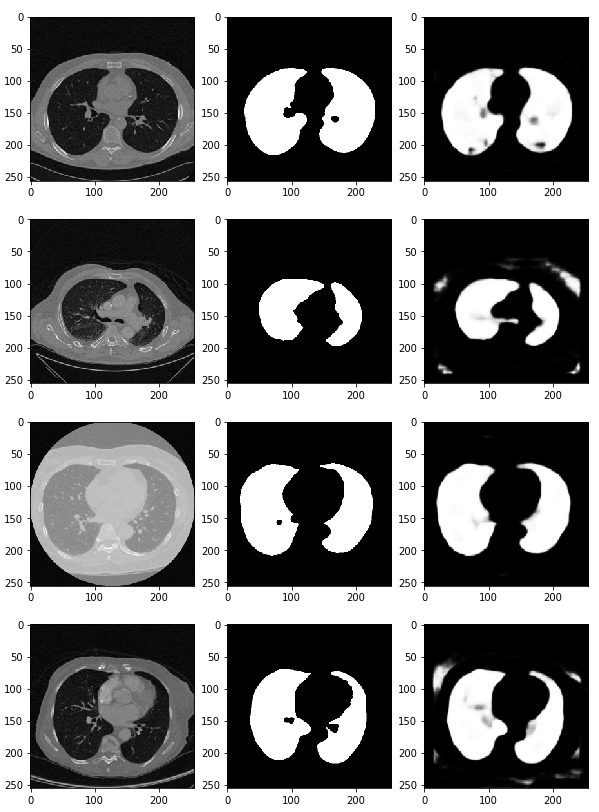

preds = model.predict(x_val) # predict 함수를 통해 (x_val) 검증한다

fig, ax = plt.subplots(len(x_val), 3, figsize=(10, 100))

for i, pred in enumerate(preds):

ax[i, 0].imshow(x_val[i].squeeze(), cmap='gray') # 첫 번째 열에는 CT 데이터(x_val[i])를 삽입

ax[i, 1].imshow(y_val[i].squeeze(), cmap='gray') # 두 번째 열에는 정답 데이터를 넣는다.

ax[i, 2].imshow(pred.squeeze(), cmap='gray') # 세 번째 열에는 우리가 예측한 결과값을 그려본다.

# 이러한 딥러닝을 활용하여 산소의 수치, 적혈구, 백혈구의 농도 등 수치적 데이터를 가지고 예측하는 방법도 존재함.